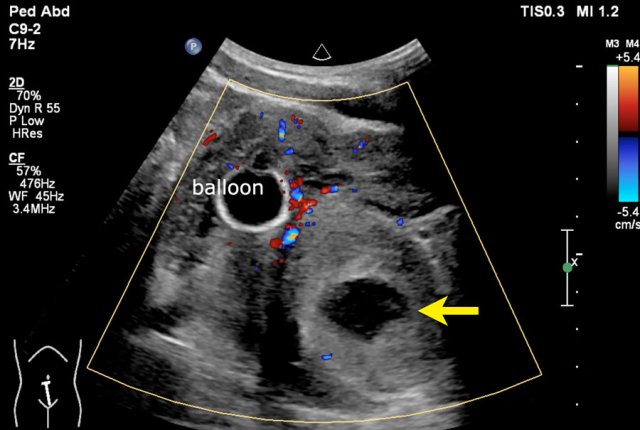

Example 1

A fifteen-year-old boy with a tumor with a small cystic part (arrow) is seen near the bladder.

Balloon of a catheter in the bladder.